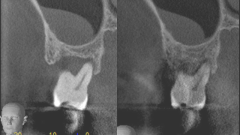

パッチテクニック症例2

治療前

治療前 治療後

治療後

◆治療内容

歯周病で失われた歯肉や歯槽骨などの歯周組織を罹患前の状態にまで改善できます。 歯槽骨の再生とともに歯根膜空隙も再生された例も確認されています。

◆リスク

・感染リスクが高まる

・瘢痕による審美性の悪化

◆治療費

保険適用外 50,000円(税別)